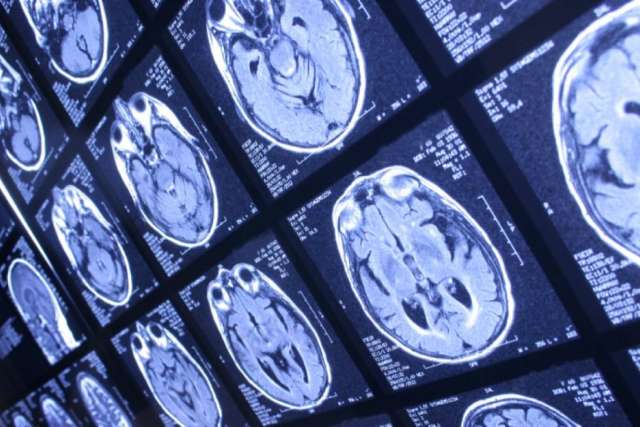

Examination is crucial, Dr. Mendez says. A clinical diagnosis is followed with brain imaging to pinpoint the area of disturbance. The location and underlying cause of the problem can affect the course of the condition and whether resulting deficits are permanent.